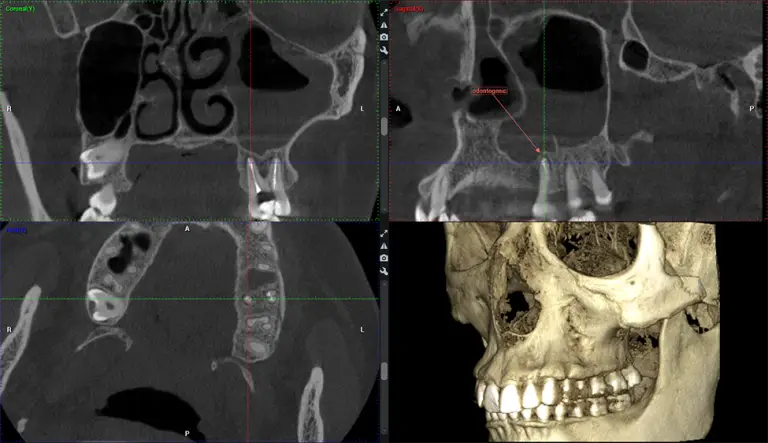

Dr. G Dental Studio is proud to welcome patients from Doral, FL. Our Miami office offers a full range of services for Doral residents — including cosmetic dentistry, dental implants, porcelain veneers, root canals, braces, wisdom tooth removal, and 3D CBCT imaging. Conveniently located just a short drive from Doral with easy parking and flexible appointment times. Call (305) 217-6453 to schedule your visit.